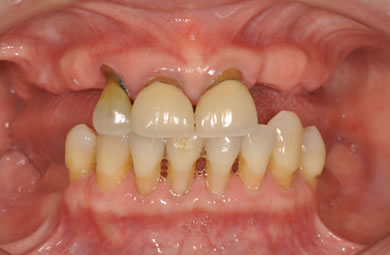

骨再生スピードインプラント治療+AGC連結セラミック治療

| 性別/年齢 | 女性 / 66歳 | ||||||||||||||||||||||||||||||||

| 主訴 | 他院で骨の量が足りずインプラントは難しいと言われ、入れ歯を使用していたが、やはりインプラント治療をうけたい。 | ||||||||||||||||||||||||||||||||

| 治療方針 | 上顎の歯周組織がかなり侵襲されているため、ソケットリフト法にて骨を回復させ、機能的回復だけでなく審美的回復も行うためにAGCハイブリッド連結ブリッジにて補綴処置を行う。 | ||||||||||||||||||||||||||||||||

| 治療内容 | インプラント12本(ソケットリフト+抜歯即日スピードインプラント)、ハイブリッドセラミック8本、AGCハイブリッドセラミック連結ブリッジ1装置、テンポラリーインプラント2本、遊離歯肉移植術 | ||||||||||||||||||||||||||||||||